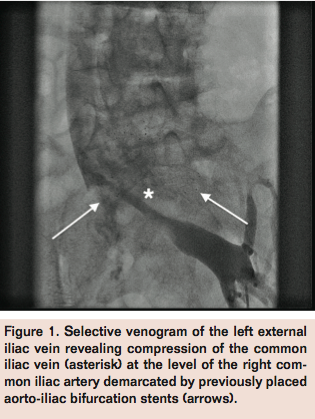

Venography via left popliteal vein access revealed a hazy filling defect in the left femoral vein. Selective venogram of the left external iliac vein was performed with the use of a glide catheter and revealed compression of the left common iliac vein at the level of the previously stented right common iliac artery (Figure 1). Intravascular ultrasound imaging of the left common iliac vein confirmed extrinsic compression (Figure 2), and identified the likely etiology of DVT.